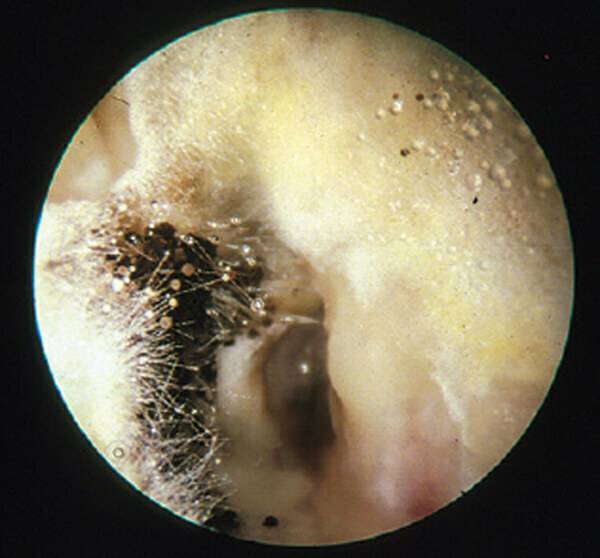

귓속에도 곰팡이가 생긴다?

우리가 귓구멍이라고 부르는 외이도는 움푹 패여있어 습기가 잘 차는 곳입니다. 이 부분에 곰팡이가 생길 수 있는데 이를 ‘외이도 진균증’이라고 합니다. 발에 무좀이 생기는 것처럼 가려움을 동반하고 심하면 통증을 일으킬 수 있는데요, 곰팡이균에 감염될 경우 항진균제를 발라 치료해야 합니다.